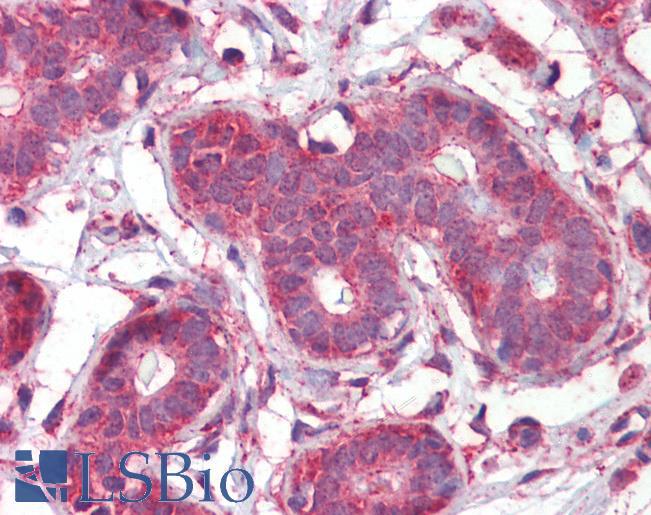

IHC Results Paraffin embedded Human Breast, Tonsil and Brain (Cortex). Recommended concentration: 2.5µg/ml. | |